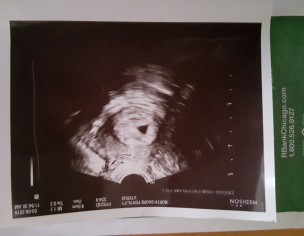

Today i had my first ultrasound also its my first time i conceive my doc said iam 5 weeks 3 days pregnant and gestational sac sizes is 8.0cm which she said is perfectly normal and good so i wanted to sure about it also next appointment is for my ultrasound is after 1 week again here is my todays ultrasound picture attached below:

Sorry doc they just give me that ultrasound pic i dont have any written report if its possible please by looking at the picture can u determine it also my doc said its 5 week and 3 days and sac size is 8.0cm?